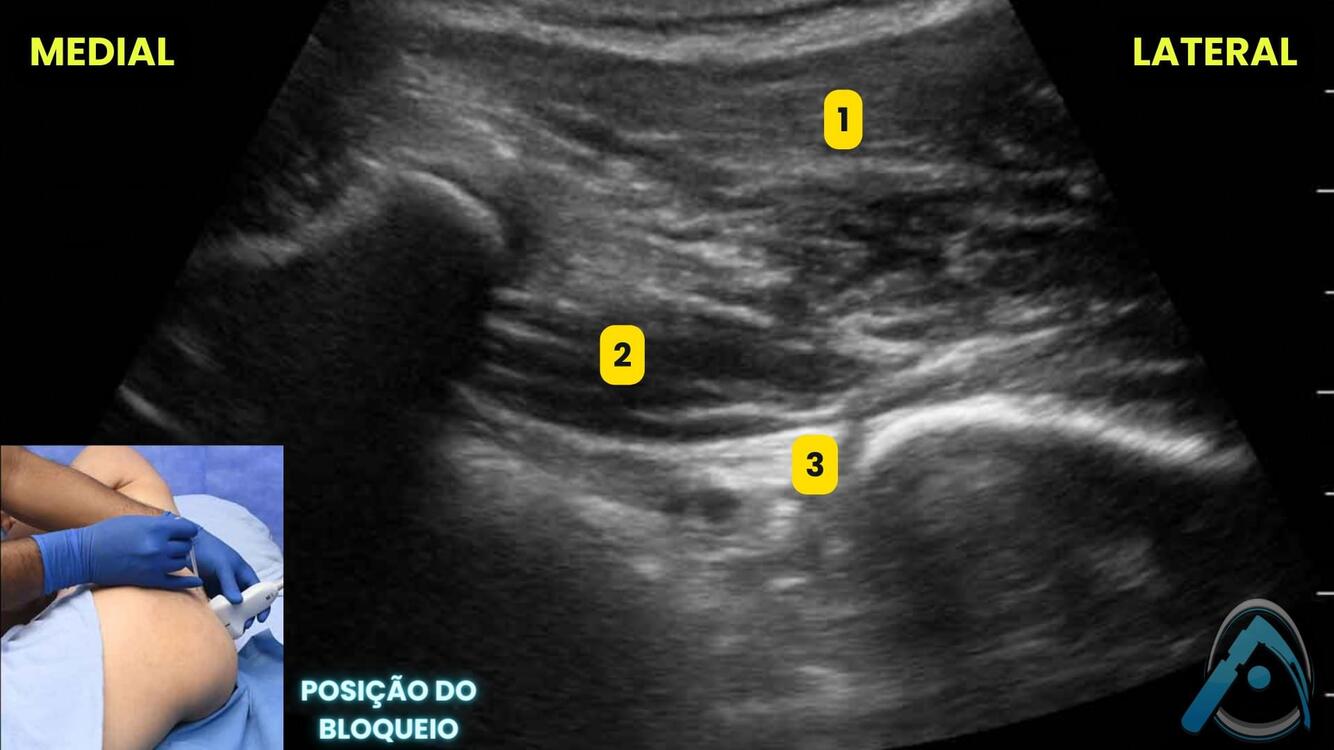

Você já viu o bloqueio do plexo sacral guiado por USG? Identifique as estruturas em destaque:

A

1 - glúteo máximo;

2 - piriforme;

3 - plexo sacral